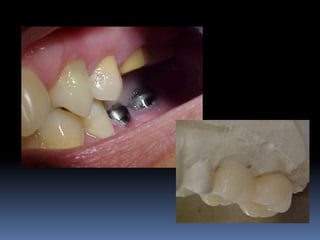

Estética durante seleção de pilares

Má posição do implante

Risco biomecânico

Perdas e fraturas